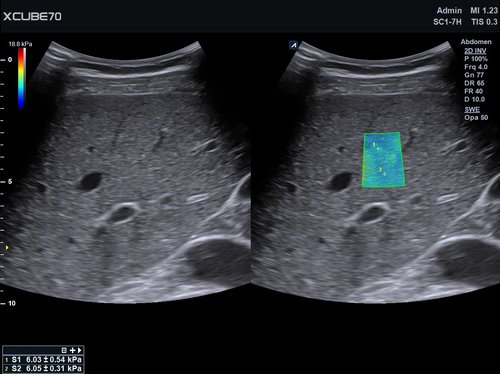

Das X-CUBE 70 fügt sich nahtlos in die neue X-CUBE Serie ein. Wie bereits das X-CUBE 90 so nutzt auch das X-CUBE 70 Farbdopplersystem die Bildverarbeitungstechnologien eines Premiumsystems, eine Vielzahl neuer Breitband-Schallköpfe mit X+ Crystal SignatureTM Technologie und neuen technischen Raffinessen.

Das X-CUBE 70 bietet modernste Technologien für eine objektive und akkurate Diagnose. Intelligente klinische Module heben das System auf ein neues diagnostisches Niveau. Es erweitert Ihre Fähigkeiten und die Bandbreite Ihrer Möglichkeiten. Dazu gehören Module wie MicroView, point Shear Wave Elastographie (pSWE), oder auch die Kontrastmittelsonographie.

• SC1-7H (1-7 MHz) für Ultraschalluntersuchungen in den Bereichen Abdomen, Geburtshilfe, Gynäkologie, Urologie, Pädiatrie, EM

• X+ Architecture mit Parallel-Beamforming für erhöhte Auflösung, Bildrate und Penetration